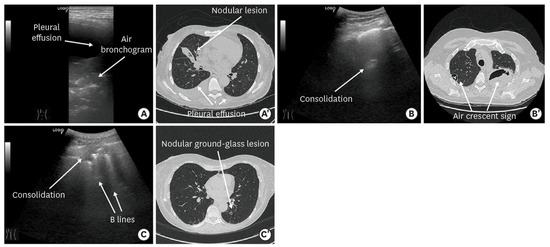

| Consolidation | Area in which lung tissue is de-aerated with density similar to parenchymal tissues [23] |

| Pleural effusion | Hypo- or anechogenic structure, delineated by the chest wall and the diaphragm [11,26] |

| B-lines | Vertical reverberation artefacts from the pleural line to the edge of the scree; laserlike, vertical hyperechogenic artefacts synchronized with pleural line [11,23,27] |

- Cocco, G.; Boccatonda, A.; Rossi, I.; D’Ardes, D.; Corvino, A.; Delli Pizzi, A.; Ucciferri, C.; Falasca, K.; Vecchiet, J. Early detection of pleuro-pulmonary tuberculosis by bedside lung ultrasound: A case report and review of literature. Clin. Case Rep. 2022, 10, e05739. [Google Scholar] [CrossRef]